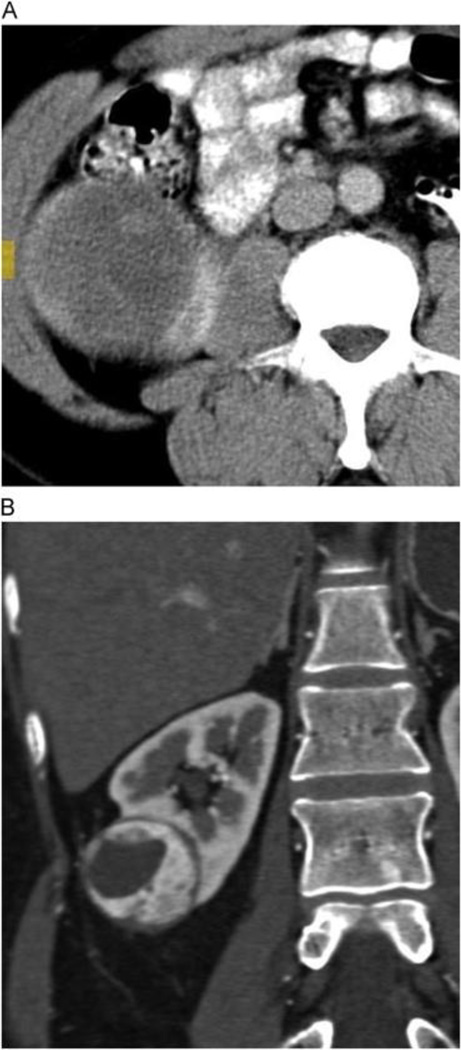

The Bosniak score is a well-established system used to assess the malignant potential of cystic renal lesions. We confirmed the strong association between Bosniak score and the likelihood of malignancy, but failed to find an association between Bosniak score and tumor histology, stage, or grade. Few studies have looked beyond the Bosniak score to investigate specific radiographic characteristics of complex renal cysts and their associations with malignancy rate and other pathological outcomes. Of the characteristics that have been studied, enhancement of the cystic septal or nodular component has been most closely associated with the likelihood of malignancy [24,25]. The current study does not address this association, as enhancement of a mural nodule upstages a lesion to Bosniak class IV, which in turn confers a very high risk of malignancy on its own. Instead, we looked at mural nodules in terms of both presence/absence and size, and found that the simple presence of a mural nodule was a strong predictor of malignancy in and of itself (Fig. 1). Additionally, there was a trend toward a higher rate of malignancy in cystic lesions with larger solid components compared with those that were primarily cystic. These observations suggest that not all radiographic features of lesion complexity should be given equal weight when determining the malignancy potential of cystic renal masses.

Fig. 1.

A 78-year-old man with complex cystic left renal mass, pathologically proven as Fuhrman grade 2 clear cell renal cell carcinoma. Precontrast (A) and corticomedullary phase post-contrast (B) enhanced images show highly vascular mural nodules that enhanced as high as 243 Hounsfield units on the arterial phase. (Color version of figure is available online.)